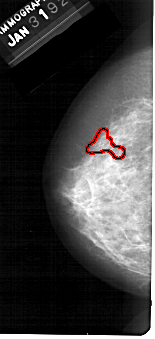

A_1130_1.LEFT_MLO

LEFT_MLO LINES 5491 PIXELS_PER_LINE 2956 BITS_PER_PIXEL 12 RESOLUTION 43.5 OVERLAY

FILE: A_1130_1.LEFT_MLO.OVERLAY

TOTAL_ABNORMALITIES 1

ABNORMALITY 1

LESION_TYPE CALCIFICATION TYPE FINE_LINEAR_BRANCHING DISTRIBUTION SEGMENTAL

ASSESSMENT 5

SUBTLETY 4

PATHOLOGY MALIGNANT

TOTAL_OUTLINES 1

BOUNDARY